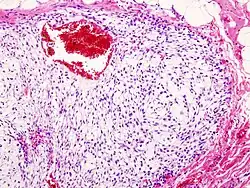

Histopathologic image of chondrosarcoma of the chest wall. Surgical resection of recurrent mass. H & E stain.